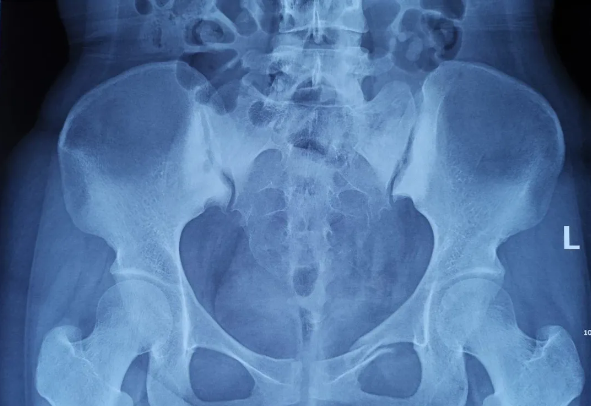

患者為22歲年輕女性,因車禍致骨盆骨折。骨盆骨折是一種復雜的創傷,傳統手術方式需要比較大的切口,而且骨盆內有大量復雜血管和神經,手術難度和風險極大,是很多骨科醫生的禁區。

在傳統骨科手術中,反復使用X線透視,有時須經常調整或更改手術固定方式,常常需要多年的臨床經驗積累,也難免意外頻發,畢竟人眼判斷和X線透視單平面觀察的局限性是客觀原因。